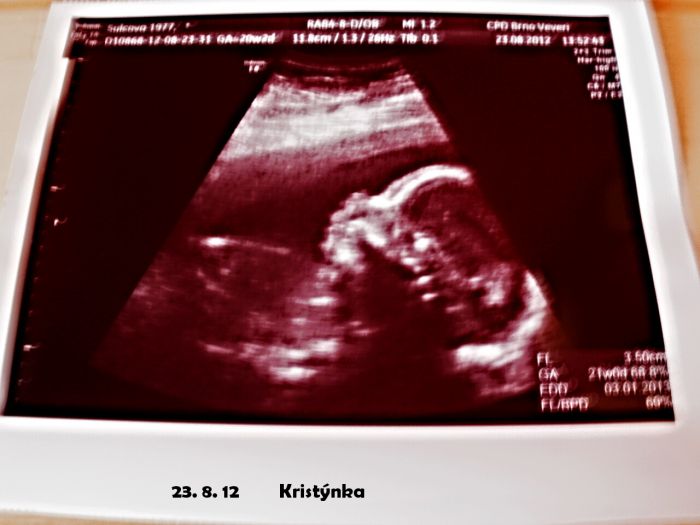

Tak ja take pridam...tady jsme ale jeste malinky...ted uz se na jedno foto nevejdeme

ted jsem si uvědomila,že jsem zapomněla přiložit fotečku naší malinké, jak nám krásně mává :) plus přiložím dnešní bazárkový ulovek, z kterého jsem paf :D samozřejmě,že růžový :DD